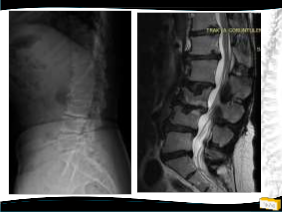

Olgu

• 64y, K

• Bel ve her iki bacak ağrısı

• NM normal

Yapılan Ameliyat: L1-L5 dekompesyon + transpediküler stabilizasyon